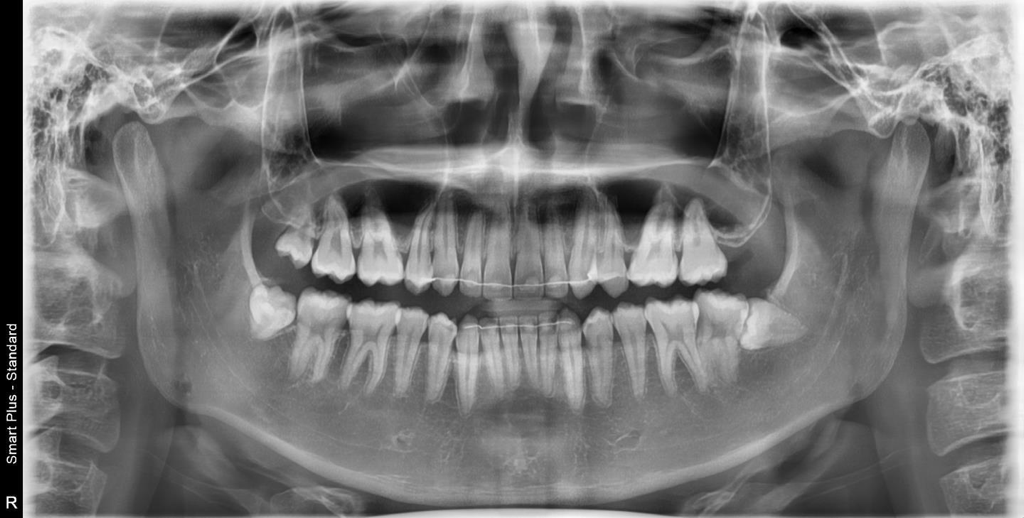

우측 하단에 보면 어금니가 45도로 휘어있는데 문제 없을까요 아니면 치료를 따로 받아야 하나요? 사랑니는 이번주 발치 예정입니다

사진상 오른쪽이 실제로는 왼쪽입니다. 왼쪽 어금니 뿌리가 약간 굽어있는 것은 큰 문제는 없습니다만 사랑니가 두번째 어금니에 매우 근접해 있었기 때문에 사랑니 발치 시 좀 더 해상도가 높은 x-ray를 찍어 충치여부를 검사해보면 좋을 것 같습니다.

사진상 왼쪽 (실제로 오른쪽 어금니) 위 어금니 뿌리 휘어진 것도 정상 범주입니다 .

현재 사랑니로 인해 앞의 어금니에 손상이 발생한 것으로 보입니다. 만약 앞의 어금니에 신경손상이 있는 경우에는 신경치료가 필요로 될수 잇습니다.